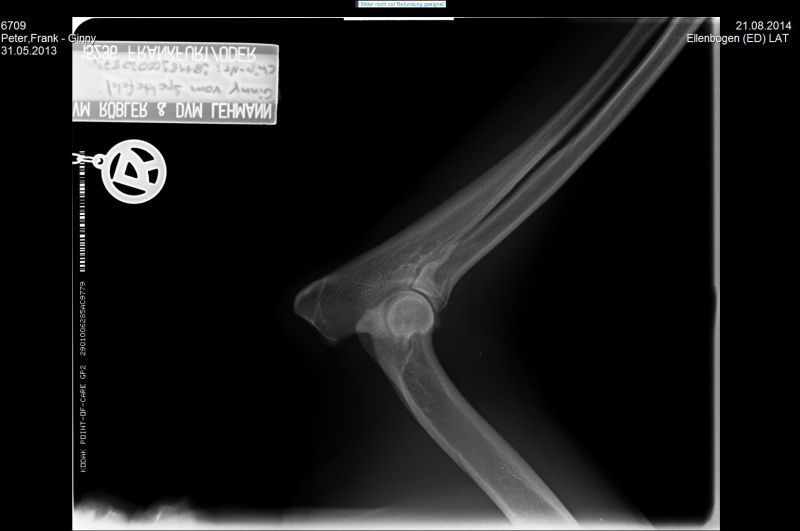

21.08.2014 - Ginny HD-und ED geröntgt - 15 Monate alt

24.08.2014 - Ginny - 15 Monate alt